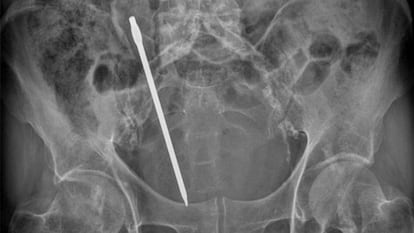

El hombre no había dicho nada de la hortaliza durante horas, pero después de la operación relató que se la había introducido “porque había leído por internet que era bueno para las hemorroides”, según recuerda la médica. La literatura científica está llena de casos similares. El Hospital Universitario Doctor Josep Trueta, en Girona, recibió un día a un hombre de 67 años que se había metido una manzana por el ano 24 horas antes. Otros casos son más extremos, como el vivido el año pasado en el Hospital Valle del Nalón, en Riaño (Asturias). Un chico de 29 años se presentó en Urgencias con dolor abdominal, tras una noche de borrachera y consumo de cocaína, según su versión. Decía no recordar nada. Los médicos le encontraron dos botes metálicos de desodorante, de unos 25 centímetros cada uno, en recto y colon.

Para Robertson, estas descripciones vinculan estos casos con prácticas aberrantes, en el contexto de un sistema "heteronormativo" cuyo único modelo válido es la relación heterosexual tradicional. “¿Por qué no situar los cuerpos extraños en el recto en el marco de prácticas sexuales consensuadas y saludables entre personas de varios géneros y orientaciones sexuales?”, se pregunta el antropólogo estadounidense. La médica de Getafe confirma que muchos pacientes son totalmente sinceros, como una mujer que llegó a Urgencias de su hospital y relató que se le había metido por completo un desodorante de bola en el recto cuando “jugaba con su pareja” en busca de placer anal. El año pasado, un hombre acudió al Hospital General Universitario Santa Lucía, en Cartagena (Murcia), tras introducirse demasiado un destornillador en el ano.

El antropólogo estadounidense subraya que no existen datos epidemiológicos, más allá de estudios aislados, así que es imposible saber la frecuencia con la que aparecen cuerpos extraños en el recto. Además, posiblemente en la literatura médica están sobrerrepresentados los casos extremos, como el del hombre que apareció en un hospital de Hong Kong con el recto perforado por una anguila. También hay descritos casos con paraguas, cañones de escopeta, cirios, pepinos, palos de escoba, tubos de aspiradora, mangos de martillo, botellas y, por supuesto, vibradores. El primer objeto en el recto descrito en una revista médica, en la estadounidense JAMA en 1919, fue un vaso. Casi cualquier objeto imaginable ha sido susceptible de dar placer anal a una persona.